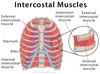

Anterior, Middle, Posterior Scalenes

ACTION

- Ipsilateral sidebending of cervical vertebra

- Reverse action: elevate first and second rib during inspiration

PROXIMAL

Anterior: transverse process CV3-CV6

Middle: post tubercles transverse process CV5-CV7

Posterior: post tubercles transverse process CV5-CV7

DISTAL

Anterior: 1st rib

Middle: sup surface 1st rib

Posterior: 2nd rib

INNERVATION

Anterior : C4-C6 ventral rami

Middle : ventral rami C3-C8

Posterior : ventral rami C7, C8